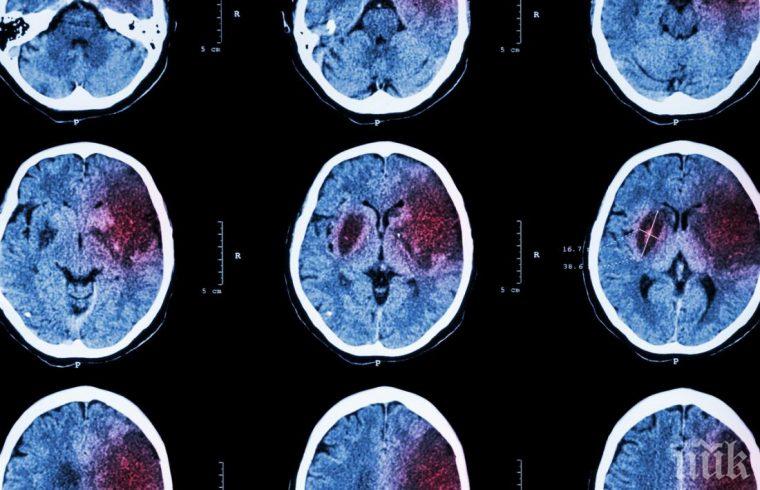

"В последните няколко години имаме категорични данни по съдови територии каква е заболеваемостта и смъртността. Данните са приблизително 11 хиляди мозъчни инсулта и 10 хиляди инфаркта на година."

"Инсултите са малко повече, това е някаква българска специфична особеност. В Европа е точно обратното. Обикновено инфарктите са малко повече от инсултите, но може би е въпрос на начин на живот, липса на профилактика", отбеляза Петров.